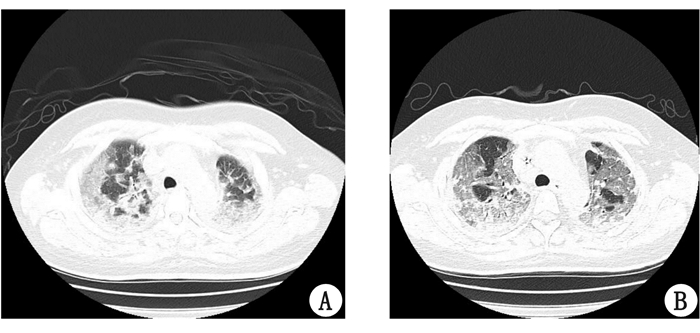

患者,女性,41岁,因“外阴部接触百草枯18 d,胸闷气喘4 d”入院。半月前患者丈夫因家庭矛盾,反复四次将市售50 mL共两瓶20%浓度的百草枯涂抹于患者内裤。患者出现外阴部瘙痒、破溃,予以外阴部局部药物治疗,未见好转。病程第13天患者出现咳嗽、胸闷、活动后气喘等症状,胸部CT提示:两肺弥漫性病变,转至本院就诊。查体:T37.0 ℃,P80次/min,R31次/min,Bp120/70 mmHg (1 mmHg=0.133 Kpa),SPO2:74%。呼吸急促,两下肺少许湿啰音,外阴部皮肤破溃、糜烂、红肿。辅助检查:动脉血气pH 7.45,PCO2 33 mmHg,PO2 38 mmHg (吸空气)。肾功能:肌酐268.8 μmol/L。入院时半定量尿液百草枯浓度:1~5 mg/L (连二亚硫酸钠法),定量血液百草枯浓度0.165 mg/L (高效液相色谱质谱联用法)。诊断:急性百草枯中毒(重度),急性肺损伤,急性肾损伤,Ⅰ型呼吸衰竭。予以糖皮质激素80 mg/d、还原型谷胱甘肽1.8 g/d、依达拉奉30 mg (2次/d)和维生素C 10 g/d等治疗。病程第19天患者肌酐恢复正常,但呼吸困难进行性加重,发绀明显,动脉血气示PO2 30 mmHg (吸空气),复查胸部CT两肺呈弥漫性磨玻璃样改变,斑片状密度增高和间质性纤维化,且有明显进展(图 1)。血管外肺水指数(extravascular lung water index,ELWI)呈动态增高趋势,给予无创机械通气及面罩给氧。病程第25天,患者病情进一步恶化,面罩吸氧10 L/min条件下,PO2 29 mmHg。患者出现神志模糊,家属拒绝气管插管、有创机械通气、ECMO等积极治疗手段,自动出院。电话随访,患者出院当天死亡。

| A:7月8日;B:7月13日 图 1 肺部CT示两肺弥漫性毛玻璃影和间质性肺炎改变 |

经消化道摄入是百草枯中毒的主要原因,经皮肤、静脉注射以及肌肉注射致百草枯中毒也有报道。本例中毒是他人将百草枯故意反复多次大量涂布于患者内裤所致,虽然接触面积较小,但存在局部皮肤长时间接触。早期症状隐匿,主要表现为会阴部疼痛破溃。气促、呼吸困难等肺部症状至病程的第13天逐渐出现,此时胸部CT检查,两肺呈弥漫性磨玻璃样改变。入院后结合体液毒物检测,明确诊断为百草枯中毒。肺部病变的出现时间较口服摄入的常见病程(3~5 d)明显滞后。局部持续吸收和中毒途径的隐匿是导致诊断延误的主要原因。虽经积极治疗,但病程第25天患者因呼吸衰竭而死亡。会阴部为毒物常规不会接触到的部位,多为意外接触,文献报道一例患者不慎将20 mL百草枯洒于大腿内侧及阴囊处,早期表现为阴茎、阴囊破溃,最终因呼吸衰竭而死亡。亦有报道一例患者因银屑病自行涂抹百草枯治疗,早期表现为85%的皮肤破溃、疼痛,后期因呼吸衰竭而死亡。本院一例36岁女性,不慎将20%百草枯50 mL泼洒至左下肢皮肤,2 h后至医院彻底洗消皮肤,无破溃,观察20 d,肝肾功能及胸部CT无异常。本例中百草枯中毒为会阴部长时间、反复多次接触所致,经医学伦理委员会批准(南医大伦审(2016)285号),家属签署知情同意书后,予以报道。百草枯可以通过会阴部皮肤黏膜吸收引起严重中毒。当患者出现隐匿部位破溃合并无法解释的症状体征以及实验室检查和/或影像学改变时,急诊医生应警惕中毒发生。同时应结合毒物学检测,追问病史,明确诊断,防止误诊。